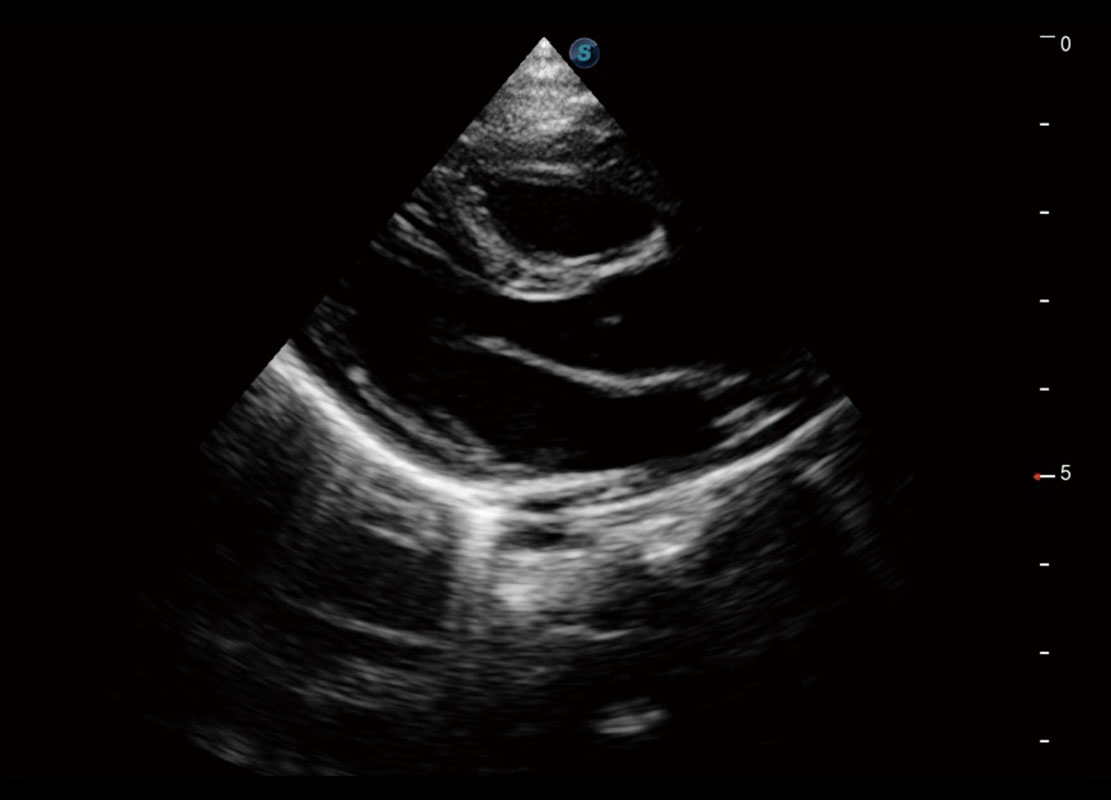

胎心筛查

P60搭载一系列胎儿心脏成像技术,实现精细的胎儿心脏评估。

• 胎心容积成像